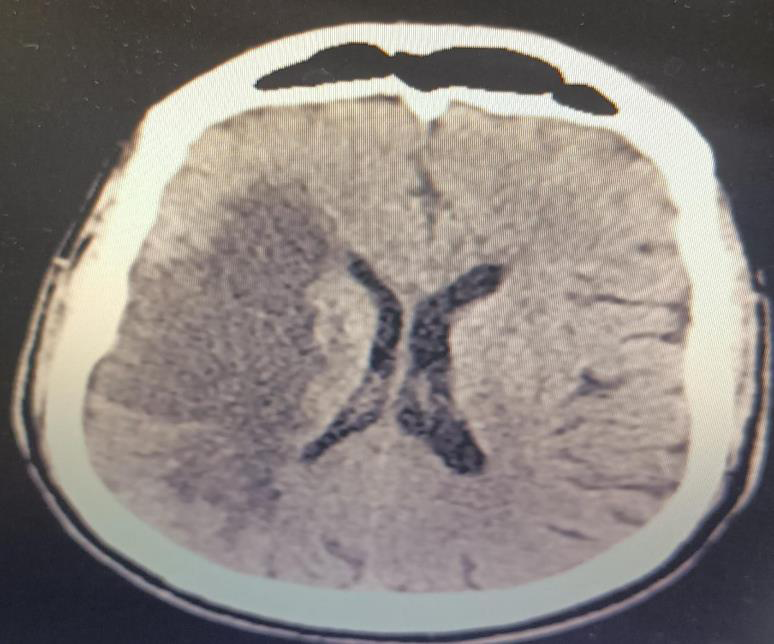

With low GCS, emergent computer tomography (CT) of brain was

performed which showed subtle hyperintensities in the right posterior

peninsular white matter suggestive of minimal hemorrhages within

the infarct with mild mass effect on the right lateral ventricle with no

midline shift. [Figure 2]

Figure 2:CT brain- showing wedge shaped hypodensity involving right

frontal, temporal and posterior front- parietal regions-likely infarct with mild

mass effect on right lateral ventricle.